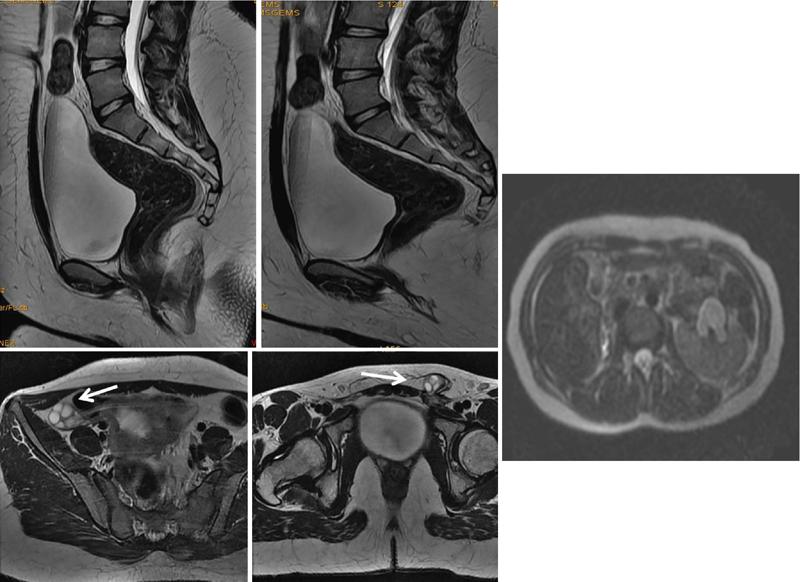

MÜLLERIAN DUCT ANOMALIES Rajani Gorantla Müllerian ducts are a pair of tubular structures that give rise to uterus, cervix, fallopian tubes and upper two-thirds of vagina. Disruption or failure of normal development can result in occurrence of Müllerian duct anomalies (MDAs). These are commonly associated with other congenital anomalies of urinary tract and ovaries due to the close relationship between the development of mesonephric and paramesonephric ducts; few patients also have associated skeletal system anomalies. The prevalence of MDAs in an unselected population was 5.5%; 8% among the infertile women, 12.3% in women with a history of recurrent pregnancy loss and 24.5% in women with miscarriage and infertility. Most of the patients with MDAs are asymptomatic and found incidentally on imaging for any other gynaecological problems, in evaluation of a patient with renal, skeletal or abdominal wall abnormalities. In symptomatic women, complains are related to the type, severity, obstructive anomaly or nonobstructive anomaly. The symptoms can be obstetric or gynaecological related, includes recurrent spontaneous abortions, infertility, preterm labour, intrauterine growth restriction and abnormal foetal lie. Few adolescent girls may present with primary amenorrhoea, hypomenorrhoea, abnormal vaginal bleeding, cyclical pain and mass. Rarely they can present with pelvic inflammatory disease with abnormal vaginal discharge, dyspareunia and urinary tract infections. The female reproductive system develops from a pair of Müllerian or paramesonephric ducts, urogenital sinus and vaginal plate. The ovaries develop separately from the primordial ridge. It is of great importance to understand the normal stages of development, as failure or interruption of any of these stages can lead to a simple to complex spectrum of anomalies. The three stages of Müllerian duct development include: At 6–10 weeks of gestation age, two paired Müllerian ducts and Wolffian ducts formation occurs. When Y chromosome factor (testicular determining factor) is absent, the Wolffian ducts undergo degeneration. The Müllerian ducts further elongate caudally and cross the Wolffian ducts to fuse in the midline. At 10–13 weeks of gestation age, caudal and lateral fusion of the two Müllerian ducts forms primitive uterovaginal canal, which is possessed of solid tissue initially located side by side and further internal canalization leads to the formation of two channels/canals divided by a septum. At this stage, there is reabsorption of the caudal septum and forms single cervical canal and vagina lumen. In around 15–20 weeks of gestation age, complete resorption of the septum takes place in a caudocranial direction from the isthmus to fundus and development of single endometrial cavity results. The fused caudal part of Müllerian ducts gives rise to the uterus, cervix and upper two-thirds of vagina; the unfused cranial part forms the fallopian tubes (Fig. 11.14.1.1). The lower vagina develops from the urogenital sinus, which is separated from the rectum by urorectal septum around 7 weeks of gestation age. The primitive uterovaginal canal embeds into the dorsal wall of urogenital sinus and forms Muller’s tubercle. Around 13 weeks of gestation, two solid masses known as sinovaginal bulbs originate from the upper part of the Muller’s tubercle, further proliferate into the caudal end of the uterovaginal canal to become a solid vaginal plate. Later canalization or degeneration of the central cells of the vaginal plate forms the lower vagina, which is usually completed by 20 weeks’ gestation. The vertical fusion of the upper and lower vagina occurs with resorption of tissue in between and forms single vaginal cavity (Fig. 11.14.1.2). The vaginal lumen is separated from the urogenital sinus by the hymenal membrane. Just before birth, the hymen normally ruptures due to retrogression of the central epithelial cells. However, a thin fold of mucous membrane persists around the vaginal introitus. The ovaries develop separately from migration of primordial germ cells to the genital ridge. Ureteric buds develop separately and concurrently. So renal anomalies are most commonly associated with MDAs with an association of 30%–50%. Various classification systems have been proposed over the past several decades to describe MDAs. Ideally, same classification system needs to be followed by a gynaecologist, surgeon and radiologist for better communication. Buttram and Gibbons classification was suggested in 1979, and it was based upon the level of failure in normal development and segregate the anomalies into groups with similar clinical manifestations, treatment, and prognosis for foetal salvage. According to Buttram and Gibbons, the uterine anomalies were classified into six classes as described in Table 11.14.1.1. The drawback is the lack of classification of vaginal and other anomalies separately. The ASRM (previously the American Fertility Society – AFS) classification system is the most widely accepted classification worldwide over the past years and was introduced in 1988. According to this classification, MDAs are classified into seven classes (class I to class VII) as mentioned in Table 11.14.1.2. However, several limitations have been described by Grimbizis and Campo in 2010 (Fig. 11.14.1.3). The drawbacks of the ASRM classification system are as follows: Hence in 2016, an updated classification of uterine septum, that is ASRM-2016 was proposed and officially approved morphometric criteria are given for distinguishing between septate, normal/arcuate and bicornuate uteri (Table 11.14.1.3). The VCUAM classification was proposed in the year 2005. The main concern is to provide a simple, systematic, clinical classification in addition to providing a precise reflection of the entire malformation. The female genital organs were divided into the following subgroups in accordance with the anatomy: vagina (V), cervix (C), uterus (U) and adnexa (A). Associated malformations were assigned to a subgroup (M) relative to each specific organ. The disadvantage is due to its inherent complexity, and more than 56,700 individual combinations of anomalies are possible. ESHRE and ESGE established a common working group named CONgenital UTerine Anomalies (CONUTA) in order to devise an improved classification system (Table 11.14.1.4). It was published in 2013. Anatomy is the basis for systemic categorization of the MDAs. The subclasses are divided by the different degrees of uterine deformity and their clinical significance (Fig. 11.14.1.4). Cervical and vaginal anomalies are classified into independent supplementary subclasses (Figs. 11.14.1.5–11.14.1.6). For most of the clinicians, it helped as starting point for the development of guidelines for their diagnosis and treatment. The malformations are graded according to severity, U0–U5, C0–C4 and V0–V4, with U5, C4 and V4 being more severe. Class U3 incorporates bicorporeal fusion defects (didelphys and bicornuate) as this was considered as a more functional mode of classification. Arcuate uterus was not included separately, but this is categorized under normal variant into class U1c. Recent studies have demonstrated that the ESHRE/ESGE system provides an effective and comprehensive classification for almost all the currently known MDAs and overcomes the limits of previous classifications. However, there is a relative overdiagnosis of septate uterus with the application of ESHRE–ESGE criteria has been reported and which potentially might lead to unnecessary surgical overtreatment. C0 C1 C2 Normal cervix Septate cervix Double ‘normal’ cervix C3 C4 Unilateral cervical aplasia Cervical aplasia U4 V0 V1 V2 V3 Normal vagina Longitudinal nonobstructing vaginal septum Longitudinal obstructing vaginal septum Transverse vaginal septum and/or imperforate hymen V4 Vaginal aplasia C MDAs’ characterization and classification is of great significance, as the treatment is determined by the type and severity of abnormality. The various imaging modalities available include: HSG was the most recognized imaging modality, earlier to the development of the ultrasonography (USG) and MRI. It is an invasive fluoroscopic-guided procedure for uterine and tubal assessment, and is performed during the midproliferative phase of the cycle, ideally between days 7 and 10 of the cycle when endometrium is thin. Fluoroscopic spot images obtained to evaluate uterine configuration, uterine filling defects and fallopian tube patency. HSG allows evaluation of only the component of the uterine cavity that communicates with the cervix. The anatomic information about myometrium and external fundal contour will not be provided by HSG. The diagnostic criteria used to diagnose MDAs on HSG include: HSG findings of different MDAs are described in Table 11.14.1.5 and Fig. 11.14.1.10. Virtual HSG is a noninvasive technique performed by using a computed tomography (CT) scanner, done 45 s after the contrast material instillation begins. Contraindications are similar to those for HSG and include pregnancy and active pelvic infection. There is no necessity for retraction of the uterus or manipulation of the cervix. The procedure is quick, easy and prophylactic administration of antibiotics is not required. The use of a power injector helps to ensure a steady low pressure of instillation. The procedure is less painful, more comfortable and easily tolerated by patients than conventional HSG. Radiation exposure sometimes requires cervical clamping, which may result in complications such as bleeding and infection. Transabdominal pelvic ultrasound can diagnose uterine anomalies with accuracy rate of 47%. Two-dimensional transvaginal ultrasound (TVUS) has high sensitivity and specificity than transabdominal study and provided some information about external and internal fundal contours. The detection rate is high if the scan is performed in secretory phase due to better visualization of endometrium. Three-dimensional USG shows great accuracy than 2D USG in evaluation of the uterine morphology. The technique of 3D USG varies with different vendors. It displays both the external and internal fundal contours and lower uterine segment by acquisition of single coronal view of uterus (c-view) (Fig. 11.14.1.11). The only disadvantage is that it is transvaginal study and shall not be done in paediatric age group and sexually inactive women. Three-dimensional TVUS has become the first line of screening tool in most of the infertility clinics as it is noninvasive, faster, repeatable, allows storage of volume data and has multiplanar capability for systematic evaluation of the uterine and cervical cavities. The salient features of various Müllerian anomalies on 3D USG are described in Table 11.14.1.6 with images. Three-dimensional ultrasound is combined with sonosalpingography in this technique and provides better delineation of the uterine morphology. It is a less invasive procedure done in proliferative phase with instillation of saline into the uterine cavity and assessment of the uterus will be done. MRI is a universally accepted imaging modality in the documentation of MDAs and accuracy rate of 100% have been reported. MRI provides excellent delineation of both the internal and external uterine anatomies. T2-weighted (T2W) images are the mainstay of pelvic imaging and are performed without fat suppression. T1-weighted (T1W) images are mainly for the haemorrhagic content. The disadvantages of MRI include time-consuming procedure, not cost-effective, large body habitus, pacemakers, recent surgical history and claustrophobia. The current and proposed MRI protocol given by the European Society of Urology (ESUR-MRI protocol) intends a dedicated evaluation of MDAs as mentioned below (Fig. 11.14.1.12): Vaginal anomalies can be accurately diagnosed with the prior administration of the ultrasound gel, to distend vagina (Fig. 11.14.1.13). It will help in better diagnosis of complex vaginal anomalies, like vaginal septations or vaginal duplication. The normal MRI appearance of uterocervical canal and vagina are shown in Fig. 11.14.1.14. Uterine aplasia/hypoplasia/agenesis is class 1 MDA according to ASRM classification and U5 uterine anomaly according to ESHRE classification. It is a formation defect of the paramesonephric ducts with complete or segmental agenesis of uterus and vagina. The incidence rate is around 10%–15% of all MDAs and considered as the most severe form of uterine anomaly. Most of them have complete uterovaginal agenesis with no single completely developed uterine cavity and are associated with Mayer–Rokitansky–Küster–Hauser syndrome (MRKHS). Two types of this syndrome are depicted. The typical form or type A represents the absence or remnants of the uterus, cervix, upper two-thirds of vagina with normal ovaries and fallopian tube (Fig. 11.14.1.15). The atypical form or type B is associated with the abnormalities of the ovaries, fallopian tubes and genitourinary system (Fig. 11.14.1.16). In a few cases (approximately 10%), unilateral or bilateral uterine remnants and with or without endometrial cavity will be seen (Fig. 11.14.1.17). Most of them present with primary amenorrhoea due to complete uterovaginal agenesis and manifest as MRKHS. These patients have normal secondary sexual characteristics due to the preserved normal ovarian function and phenotype. If uterine remnants with functional cavity is present, will present with cyclical pain along with amenorrhoea due to cryptomenorrhoea and haematometra. USG is the first modality for identification of these anomalies, absence of uterus with normal ovaries is diagnostic. But, it is difficult to locate the uterine remnants and cavity due to small acoustic window. MRI is the gold standard and it classifies into uterovaginal agenesis and hypoplasia. If hypoplasia is identified, sagittal and axial sections are taken. These remnants are seen as T2 hypointense tubular structures, located in close relation to ovaries in the adnexa. Once we identify the uterine remnants, it is important to look for the functional endometrial cavity. These will have reduced endometrial and myometrial width. MRI can easily delineate the zonal anatomy due to its high soft tissue contrast resolution. The management of Müllerian agenesis consists of counselling for the patient and her parents. Some patients with MRKHS opt for creation of neovagina for normal sexual life. Various techniques are available. In the presence of a functional Müllerian remnant, regardless of whether it is communicating or not, medical suppression of menses can be initiated and should be followed by laparoscopic removal of the hypoplastic remnant. Unicornuate uterus or hemiuterus is defined as the unilateral uterine development and the contralateral Müllerian duct could be either partially formed or absent. It is a formation defect and the necessity to classify it in a different class than that of uterine agenesis, which is also a formation defect, is due to the existence of a fully developed functional uterine hemicavity. It is considered as class II anomaly according to ASRM classification and class U4 according to ESHRE classification. The frequency rate is around 20% of MDAs. Renal anomalies most often occur in association with unicornuate uterus and usually on the same side of uterine agenesis. Further unicornuate uterus is divided into two subclasses depending on the presence or absence of a functional rudimentary cavity in ESHRE classification: In ASRM classification, unicornuate uterus is divided into four subcategories: Mostly asymptomatic and presence of the noncommunicating uterine remnants will be identified at the time of infertility work up or caesarean section. If a functional cavity is present, the presentation is dysmenorrhoea or haematometra in an adolescent. The common obstetrics-related complications include abnormal foetal lie, intrauterine growth retardation, preterm delivery, placental abnormalities and uterine rupture. Gynaecological complications are ectopic pregnancy and endometriosis due to retrograde menstruation. On imaging, unicornuate uterus is seen as tubular and fusiform or banana-shaped structure at paramedian location, the endometrium is narrow and tapers to the apex with normal myometrial anatomy and reduced uterine volume. The rudimentary cavity or remnants are better depicted on 3D USG (Fig. 11.14.1.18) and MRI. However, MRI is superior to USG due to its high soft tissue resolution. The rudimentary cavity can communicate with main cavity or connected by fibrous band. The nonfunctioning cavity will be seen as T2 hypointense structure with loss of zonal anatomy (Figs 11.14.1.19 and 11.14.1.20), whereas the functioning cavity will show the deformed zonal anatomy (Fig. 11.14.1.21), and its complications like haematometra as T1/T2 hyperintense endometrial collection. Unicornuate uterus without rudimentary cavity does not require any procedure. But in the presence of communicating or noncommunicating rudimentary horn, surgical resection must be considered to prevent complications. Uterine didelphys is a class III MDA based on the ASRM classification and class U3b bicorporeal uterus according to ESHRE classification with an incidence rate of 5% among the uterine anomalies. It is a lateral fusion defect; results from complete failure of the Müllerian duct fusion. Two noncommunicating endometrial cavities with preserved zonal anatomy are seen with separate cervix. According to ESHRE classification, it is defined as external fundal indentation completely dividing the uterine corpus up to the level of external cervical os. It is most commonly associated with longitudinal vaginal septum in around 75% of cases. Some patients may show transverse vaginal septum and these will be obstructive or nonobstructive type. Renal anomalies are also commonly associated with uterine didelphys. Uterine didelphys is usually asymptomatic and diagnosed incidentally on pelvic examination or caesarean section. The uterine didelphys with obstructed vagina (Fig. 11.14.1.22) will present at adolescence as dysmenorrhoea, haematometrocolpos and haematosalpinx. Sometimes retrograde menstrual flow can cause endometriosis and pelvic adhesions. Obstetric-related complications include abortion/foetal growth restriction and poor pregnancy outcome. The uterine didelphys with obstructed hemivagina due to transverse vaginal septum and associated ipsilateral renal agenesis are the manifestations of the syndrome called obstructed hemivagina and ipsilateral renal agenesis anomaly/Herlyn–Werner–Wunderlich (HWW) syndrome (Fig. 11.14.1.23).